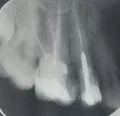

Зуб наращивали на штифт, штифт спустя годы, выпал вместе с пломбой, корень остался, нервов, естественно, нету там уже. Корень как будто гнилой, не болело ничего, сейчас уже спустя 3 дня болит на стену лезу, таблетки не помогают, что мне делать?? От чего это может быть, ведь нервов-то нету??

К сожалению, зуб удалится. Боль, скорее всего, от воспалений на верхушке зуба (киста, циста). Рекомендую вам не тянуть, боль будет только усиливаться, и к тому же обострение способствует осложнениям.